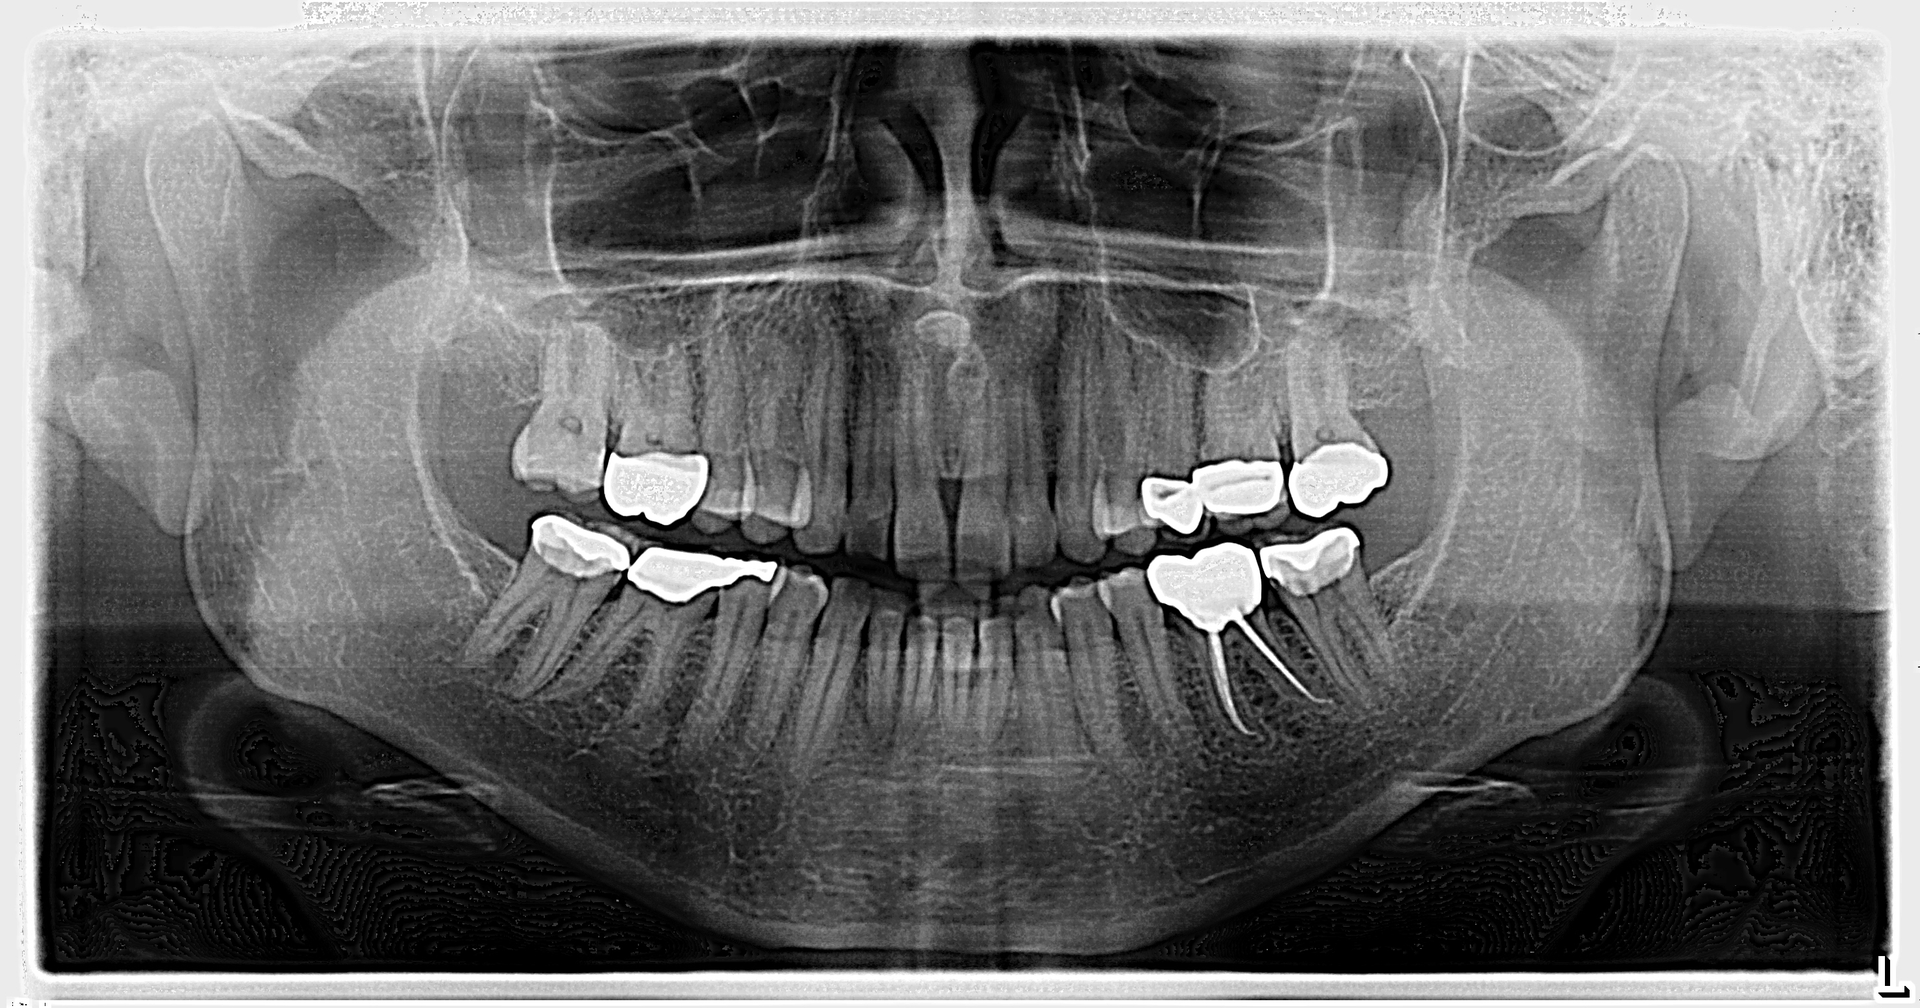

An assessment of the pan revealed two radiopaque lesions apical to the root tips of nos. 8 and 9, each measuring approximately 8 mm x 4 mm (figure 1). There was no tenderness on palpation in the generalized area. Access to a previous pan taken six years prior revealed no significant changes to the radiopacities (figure 2).

Given the location, absence of change, and shape of the lesions, the diagnosis for these lesions is mesiodens, a “supernumerary tooth located between the maxillary central incisors.”1 The lesions may occur “as single, multiple, unilateral, or bilateral (lesions); the presence of multiple supernumerary teeth is called ‘mesiodentes.’”2 By way of appearance, they typically manifest as a conical or peg-shaped form.2